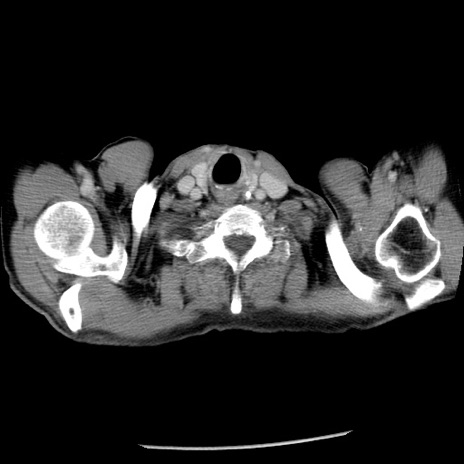

冠状断像